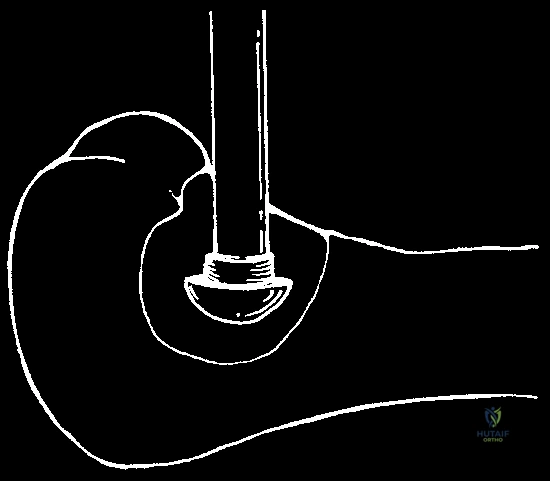

If using the direct pour technique, a sterile stainless steel funnel is placed securely into the window. Liquid nitrogen is poured slowly and continuously.

Direct pour technique: Liquid nitrogen is carefully introduced into the cavity through a sterile funnel.

The cavity fills with liquid nitrogen, initiating the rapid freeze cycle and profound thermal shock to the microscopic disease.